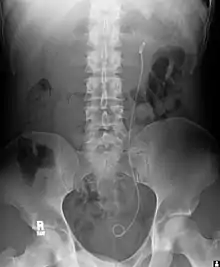

| Уретральні стенти застосовують для забезпечення прохідності уретри, порушеної, наприклад, унаслідок нирковокам'яної хвороби. Цей метод може бути тимчасовим заходом для запобігання ушкодженню заблокованої нирки до видалення каменю. | ![]() Уретральний стент, що послаблює гідронефроз нирки |